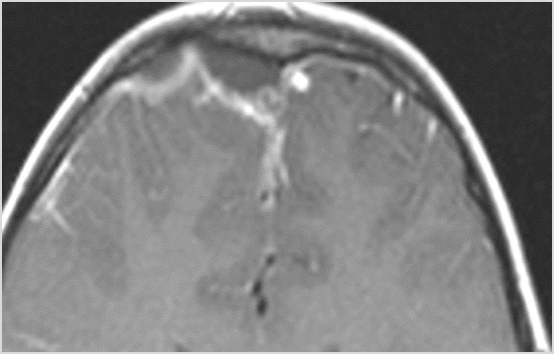

There is likely meningitis, meningoencephalitis with complicating hydrocephalus or brain herniation.